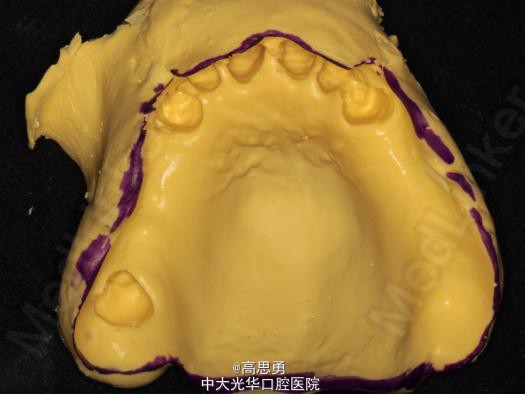

2、研究模型 调拌藻酸盐印模材料于2号成品托盘上取上下颌研究模,灌注石膏模型,研究分析、制定治疗计划,并制作个别托盘。

3、基牙预备 对#13近中、#23远中、#27近中、#34近中、#47近中常规制备支托凹,抛光。

4、工作模型 调拌藻酸盐印模材料于个别托盘上。做一定的边缘整塑,取上下颌研究模,灌注石膏模型。

5、试戴支架 检查支架的就位、固位可,无翘动,调HE,抛光,用蜡堤取颌位关系,上颌架,排牙,比色C4。